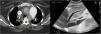

A 35-year-old woman presented to the emergency department with dyspnea and chest tightness lasting for 1 day. Computed tomographic pulmonary angiography confirmed the diagnosis of acute pulmonary embolism (Fig. 1a, yellow arrow). Venovenous extracorporeal membrane oxygenation (VV-ECMO) was implanted due to severe hypoxemia (a P/F ratio of 64 mmHg). Three days later, VV-ECMO was successfully decannulated, and an immediate ultrasound examination detected a rare morphology of ECMO-related thrombus in the inferior vena cava (IVC): a pedunculated, polypoid mobile thrombus floating with a heartbeat (Video 1 and Fig. 1b). The IVC thrombus dissipated after a 3-week standard anticoagulant treatment (Video 2). The case indicated the necessity of routine IVC ultrasound examination after the decannulation of ECMO.